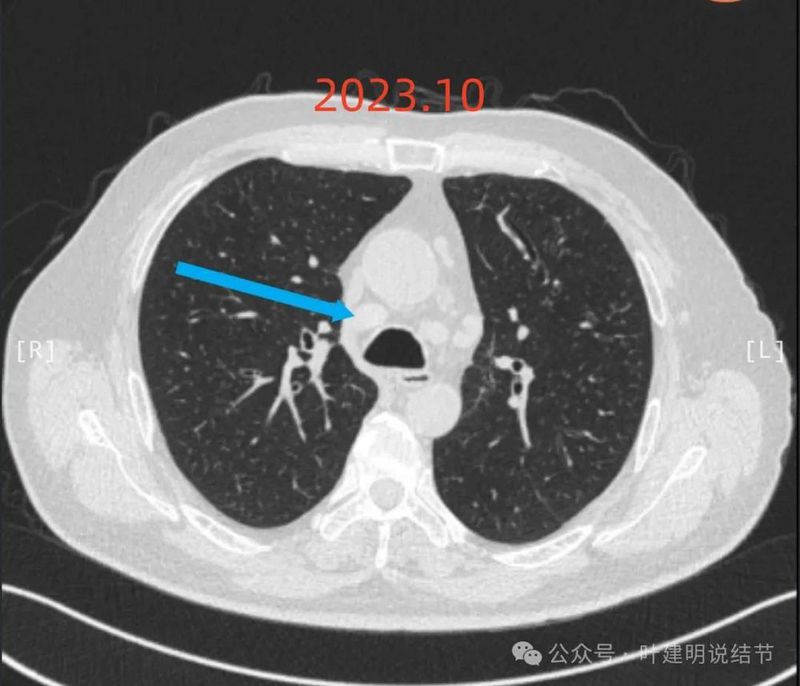

2023年10月1日 病人咳嗽不断,随后进入当地三甲医院住院诊断,按炎症处理,同时做气管镜穿刺,诊断为大肠菌肺炎,CT影像及报告见附件1 ;

2024年1月病灶较3个月前明显增大进展,是实性小结节,有微小血管走向病灶。